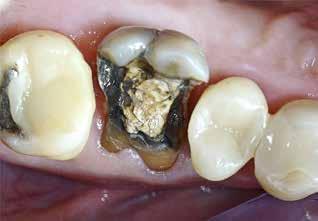

Knækket rodfil

i distal kanal -6

PATIENTTILFÆLDE

Patienten henvender sig på klinikken pga. akutte smerter fra -6. Der laves akut oplukning og findes tre kanaler. Ved udrensning i distale kanal for at finde endeligt rodmål knækker ca. 1-2 mm af fil 08 i kanalen. Patienten bliver informeret og henvist til specialtandlæge for videre behandling.

LÆRING

Det fremgår, at der er tale om en filstørrelse 08, altså den tyndeste fil, der findes. Ved flerrodede tænder med lange, krumme og/eller oblitererede (“tilgroede”) rodkanaler er risikoen for filfraktur højere.

Det anbefales derfor, at du anvender meget fleksible file, skyller kanalerne hyppigt undervejs og kasserer file, der udviser svaghedstegn (fx vrid eller buk på filens arbejdende del). Du bør desuden kassere de mindste file efter brug, da risiko for usynlige svagheder i disse er høj. Alternativt kan du henvise til en tandlæge med særlig kompetence inden for rodbehandling, hvis du vurderer, at en rodbehandling er særligt vanskelig.

Se også guiden "Sådan fjerner du et filfragment" på side 774.